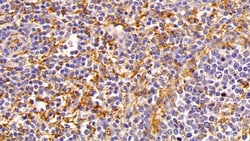

IBA1 Polyclonal Antibody for Western Blot, IHC (P)

Ionized calcium-binding adapter molecule 1 (IBA1), also known by its gene name AIF1, is a protein expressed predominantly by microglia in the brain and spinal cord. This protein belongs to the EF-hand calcium-binding protein family and plays a crucial role in microglial activation and migration in response to brain injury or neuroinflammation. IBA1's function is integral to microglial motility and phagocytic activity, facilitating the cellular response to pathogenic stimuli and promoting tissue homeostasis and repair in the central nervous system. IBA1 serves as a reliable marker for activated microglia in various neurological disorders, including Alzheimer's disease, Parkinson's disease, and multiple sclerosis, where increased expression correlates with disease progression and severity. The protein's structural features enable it to bind calcium ions, inducing conformational changes that activate signaling pathways essential for microglial function. Its expression is highly regulated by inflammatory cytokines, underpinning its role in neuroimmune responses. Due to its specific expression in microglia during pathological conditions, IBA1 is widely used in research as a marker to study microglial status and activity, and it remains a focal point for understanding microglial involvement in neurodegenerative diseases.Specifications

| Immunohistochemistry (Paraffin), Western Blot | |